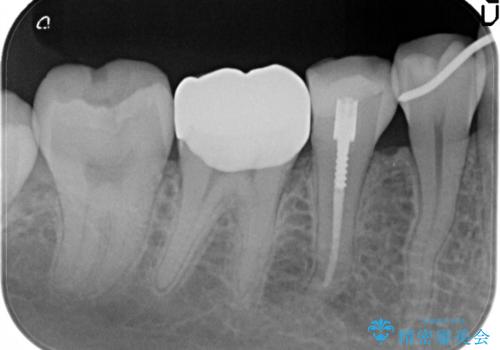

セラミッククラウンにて下顎の左右の歯にセラミッククラウンを装着する計画としました。

目立つところの銀歯がなくなり、審美的な改善ができました。